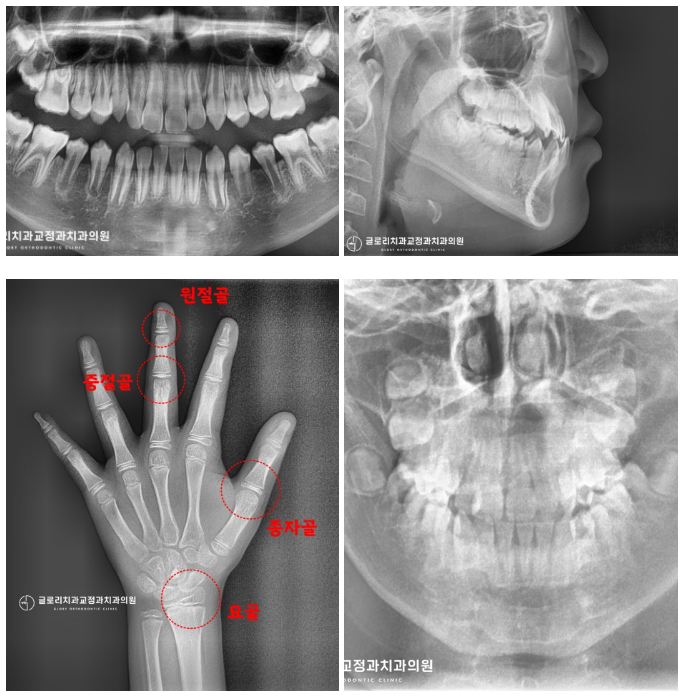

전형적인 3급 부정교합이 관찰되고 있네요.

『아랫니가 윗니를 덮고 있는

반대교합(cross bite)가 눈에 띄는데요.』

전문의 대표원장이 수완부 방사선 사진을 비롯한

여러 정밀 검진을 시행하여 확인해 봤는데요.

교정을 시작하기에 딱 적합한

시기로 확인되어 본격적인 치료 계획을

세우기로 했습니다!